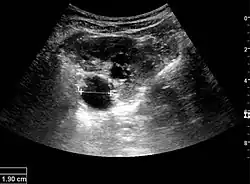

Figure 19. Centrally located stone with posterior shadowing. No hydronephrosis is present. Measurement of kidney length on the US image is illustrated by '+' and a dashed line.[1] -

Figure 20. Staghorn calculi filling the entire collecting system and creating pronounced shadowing.[1] -